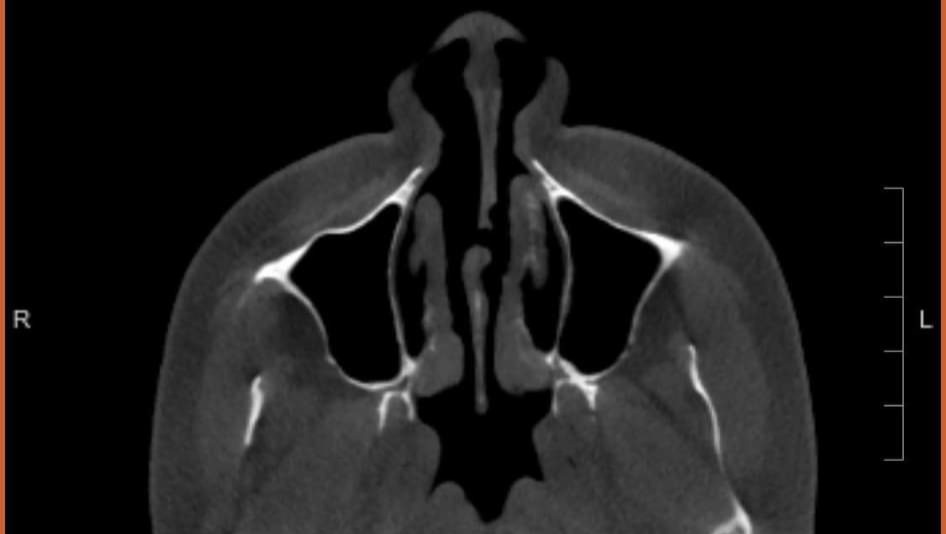

After assessing everything, Dr. Hamilton stated that Kinslee was in immediate need of septal repair. He informed us that the buttons that had been in place over the last few months had done nothing but damage the septal area even further. He added that a septal button should never be placed in any hole or perforation over 2 cm and during his initial scans and measurements found there were numerous areas of Kinslee's perforated septum that measured as big as 4 cm. He informed us that no matter how we decided to proceed, that the first thing that needed to happen was for the septal button to be removed immediately. An hour later, after what we thought would be a 10-minute consultation, Kinslee was being prepped for a procedure right there in the office in order to remove the septal button. Once the doctor removed the septal button, he did another scan and assessed the situation under camera even more extensively and told us that what we needed was just shy of a miracle. It appears that Kinslee has no cartilage left in her nose and that some would need to be taken from her ribs in order to build a new septum. At this point, Dr. Hamilton is the only doctor that has agreed to take on our case, stating that it is going to be a lot of work and may require more than 1 surgery. There was 2 hurdles standing in our way. The first being that Hamilton's surgery calendar was currently booked out through September. Working in our favor was the fact that we needed immediate action on something that should have been addressed months ago. We left that afternoon with some good answers and a lot of info, but unsure of the next steps.